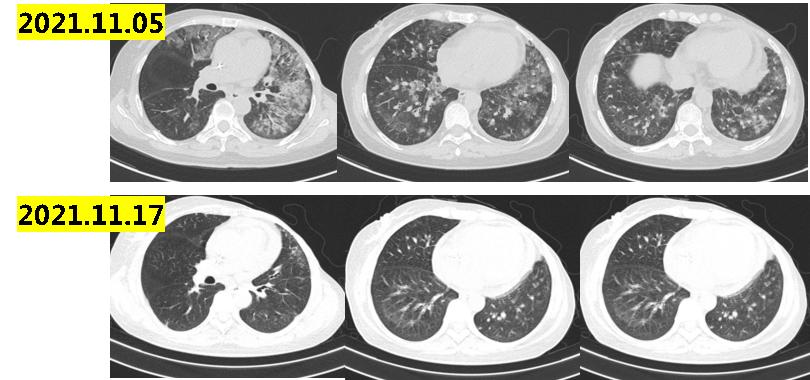

2021.11患者再次出院胸闷气喘,2021.11.05复查肺部CT示:双肺新增斑片影、小叶间隔增厚,考虑间质性炎症或感染性病变,较前新增;左肺下叶支扩伴感染,双肺散在结节影,左肺上叶新增结节,考虑转移可能;少量心包积液(图1-5)。

图1-5

讨论意见:患者长春瑞滨治疗后再次出现间质性肺炎改变,肺部CT提示病情进展,建议行抗生素+激素治疗。诊断为左乳癌综合治疗后进展(双肺、胸膜、纵隔LN、心包积液)三阴型,患者既往使用过EC-T、白蛋白紫杉醇、卡培他滨和长春瑞滨化疗方案,根据2021CSCO指南:建议患者行艾利布林或者UTD1方案化疗。艾利布林属于进口药物,价格昂贵,UTD1属于国产原研药物,但有买2赠终身的慈善政策。

行抗生素激素治疗后患者症状明显缓解,影像学提示间质性改变较前明显改善(图1-6),2021.11.23-2022.04行UTD1化疗6周期,疗效评价PR(图1-7,1-8)。

图1-6